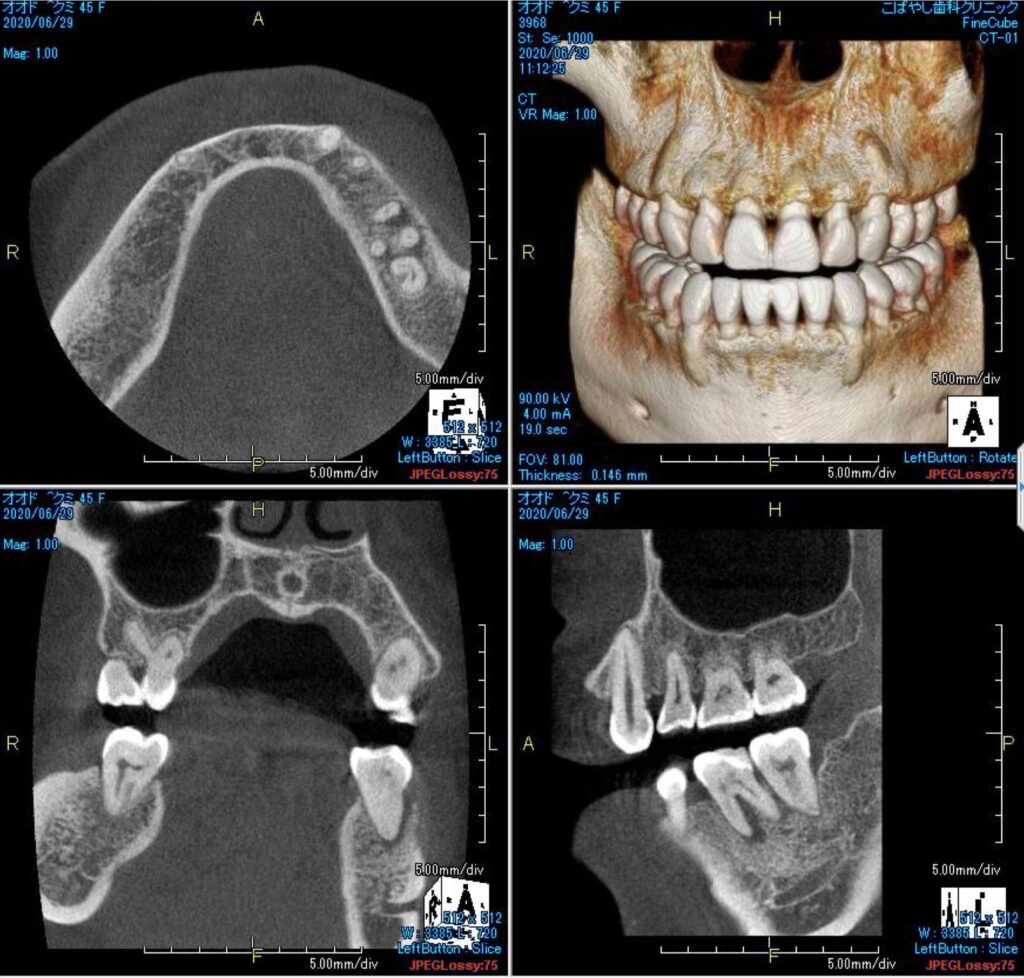

神経(歯髄)近くまたは神経自体にまで達したむし歯があるとき、外傷によって神経が露出したときに、MTAセメントという特殊なセメントを使用し、神経を残す治療です。

これまでであれば神経を除去するしかないケースでも、神経を残せる可能性があります。

神経を残すことの重要性を鑑み、当院では根管治療の前に、まずは歯髄保存療法を第一の選択肢として考えます。ただ、自費・保険から選べる根管治療とは異なり、歯髄保存療法はすべて自費診療となります。歯髄保存療法のメリットやデメリット、費用のことなどを詳しくご説明した上で、最終的には患者様に治療法を選んでいただきます。